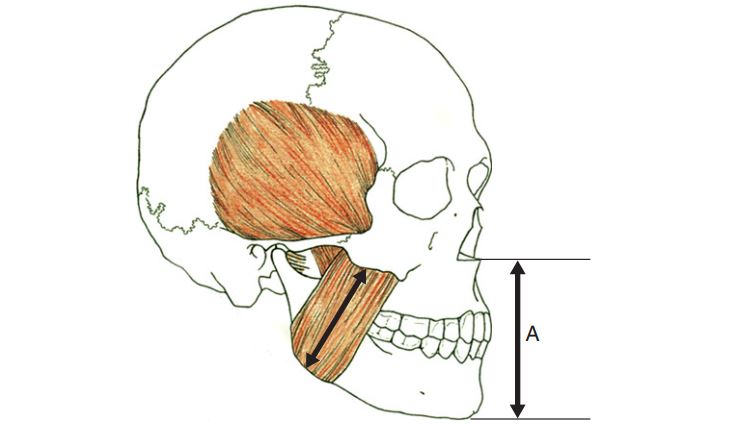

Kích thước dọc xảy ra khi răng ở trạng thái lồng múi tối đa (LMTĐ), nhưng răng không phải là yếu tố quyết định kích thước dọc mà chính chiều dài co cơ lặp đi lặp lại mới là yếu tố quan trọng xác định tương quan hai hàm, tạo nên kích thước dọc.

Kích thước (chiều dài) của các cơ nâng hàm khi co quyết định kích thước dọc cắn khớp.

Điều quan trọng cần biết về kích thước dọc là hàm dưới được hệ thống cơ nâng hàm hướng dẫn đến một vị trí và vị trí này có thể lặp lại được.

Điểm cân bằng đó (neutral point) chính là vị trí tối ưu cho hệ thống cơ co theo chu trình lặp đi lặp lại. Nếu không có răng đối thì cơ có thể co nhiều hơn, tuy nhiên sự đóng hàm theo thói quen là gần như không thể thay đổi, và nó là yếu tố quyết định KTD.